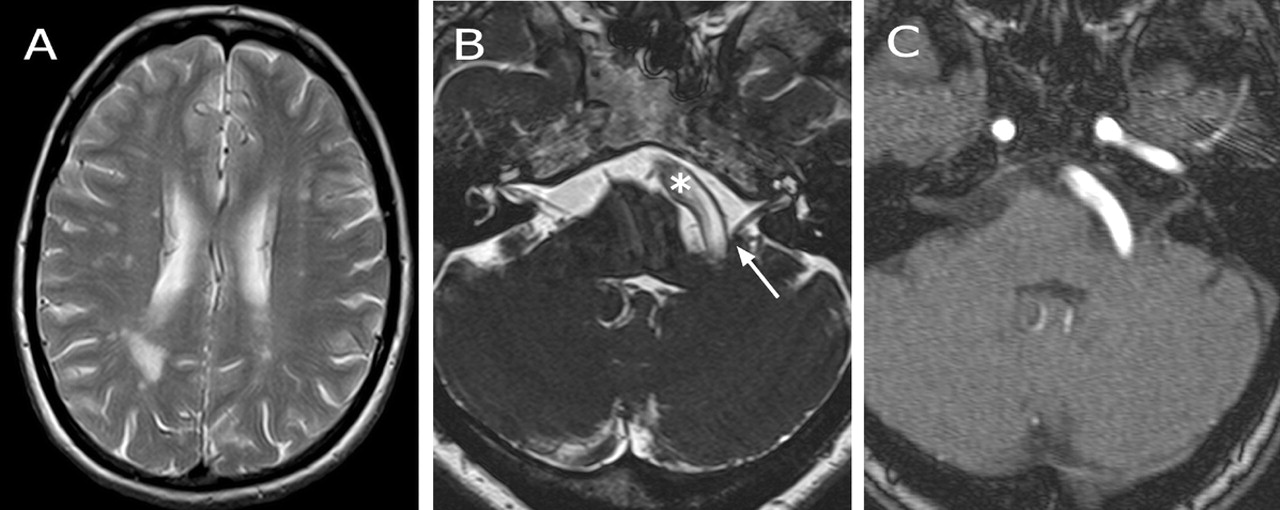

图。(一)轴向t2加权MRI显示不对称,广泛,hyperintense白质病变。(B, C) Three-dimensional-CISS成像(B,在稳态三维傅里叶变换相长干涉)和三维飞行时间MR-angiography (C)证明左第8脑神经压缩(箭头)的基底动脉因脑中风(星号)。

脑血管衬底沉积通常影响vertebrobasilar系统导致脑中风。2阵发性眩晕最可能导致megadolichobasilar压缩的蜗神经(图中,B和C),尽管在Fabry眩晕发生疾病的其他原因。